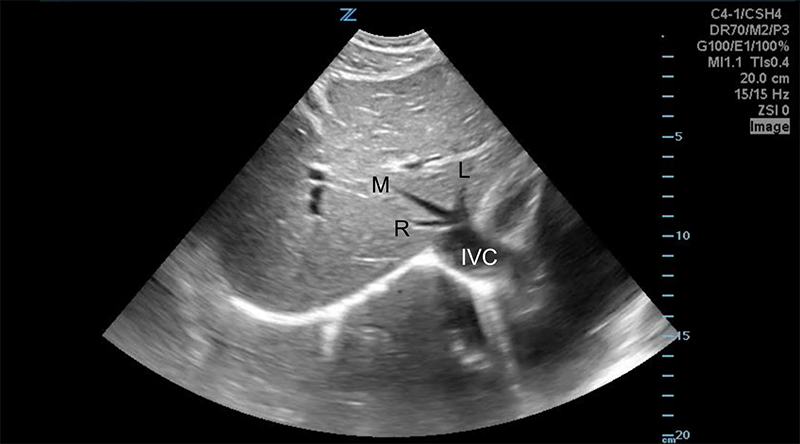

- Liver Lobes - The left and right lobes are divided by the middle hepatic vein, and the caudate lobe lies posterior to the left lobe, between the inferior vena cava (IVC) posteriorly and the ligamentum venosum anteriorly.

Figure 7. Transverse subxiphoid view of the liver. The middle hepatic vein divides the left and right lobes of the liver. The caudate lobe is located posterior to the left lobe. (R,M,L = Right, Middle, Left hepatic veins, respectively. IVC = Inferior Vena Cava)

Figure 8. Transverse subxiphoid view of the liver. Hepatic veins (orange arrows) are straight with thin walls, whereas portal veins (blue arrows) have bright walls and are more tortuous.